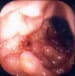

A clinical scenario that comes up not uncommonly, certainly in my business, is a patient with an upper GI bleed on aspirin. What do you do about the aspirin when that patient comes in and you find that the patient clearly has an ulcer that, in fact, may be an active bleed?

Traditional therapy would be to treat the active bleed, stabilize the patient, treat with a proton-pump inhibitor, and recommend that the patient stop the aspirin. Check for Helicobacter pylori, of course; if that's positive, you would treat. The recommendation traditionally is to stop the aspirin because it has caused harm; in fact, this may have been the teaching for quite some time. But is it the current standard? The answer is, probably not.